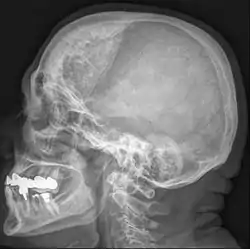

![]() فرط تعظم باطن العظم الجبهي في امرأة تبلغ من العمر 74 عاما فرط تعظم باطن العظم الجبهي في امرأة تبلغ من العمر 74 عاما | |

فرط تعظم باطن العظم الجبهي (باللاتينية: Hyperostosis frontalis interna) هو تسمك حميد شائع يحدث في الجزء الداخلي من العظم الجبهي من الجمجمة. يحدث غالبا في النساء في سن اليأس وغالبا من يكون بدون أعراض. غالبا ما يكتشف بشكل عرضي خلال الفحوص بالأشعة السينية والأشعة المقطعية للجمجمة.[1]